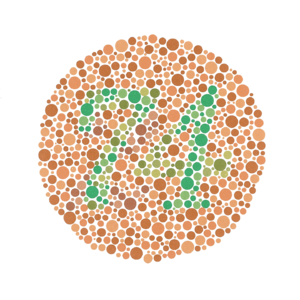

This image contains the number 37, but someone who is protanopic may not be able to see it.

This image shows a number 49, but someone who is deuteranopic may not be able to see it.